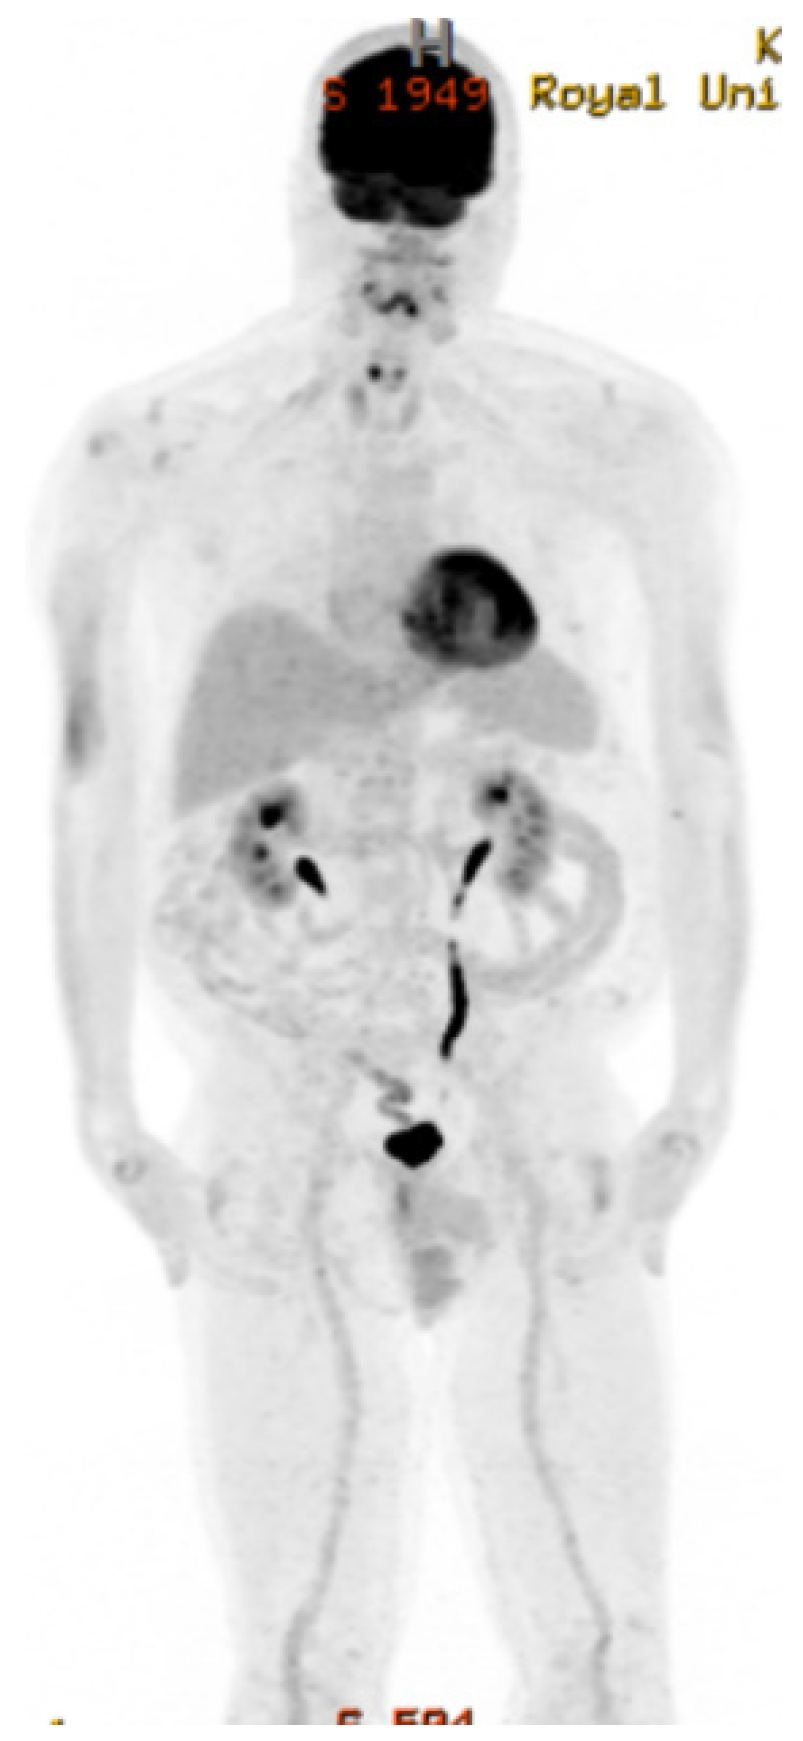

2. Case Presentation